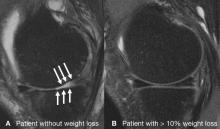

Obese people who lose a substantial amount of weight can significantly slow knee cartilage degeneration, according to a new magnetic resonance imaging (MRI) study presented today at the annual meeting of the Radiological Society of North America (RSNA).